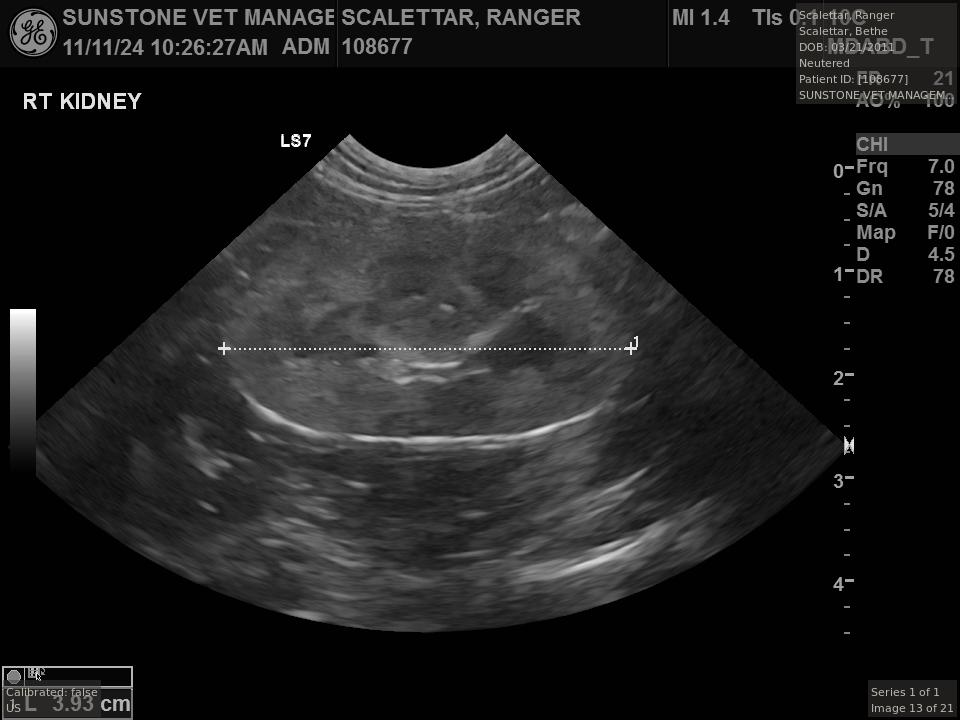

Case Study 1:

Veterinary Examination

This study describes a visit to a veterinary specialist with a cat suffering from small cell lymphoma. The visit included both X-ray and ultrasound examinations.